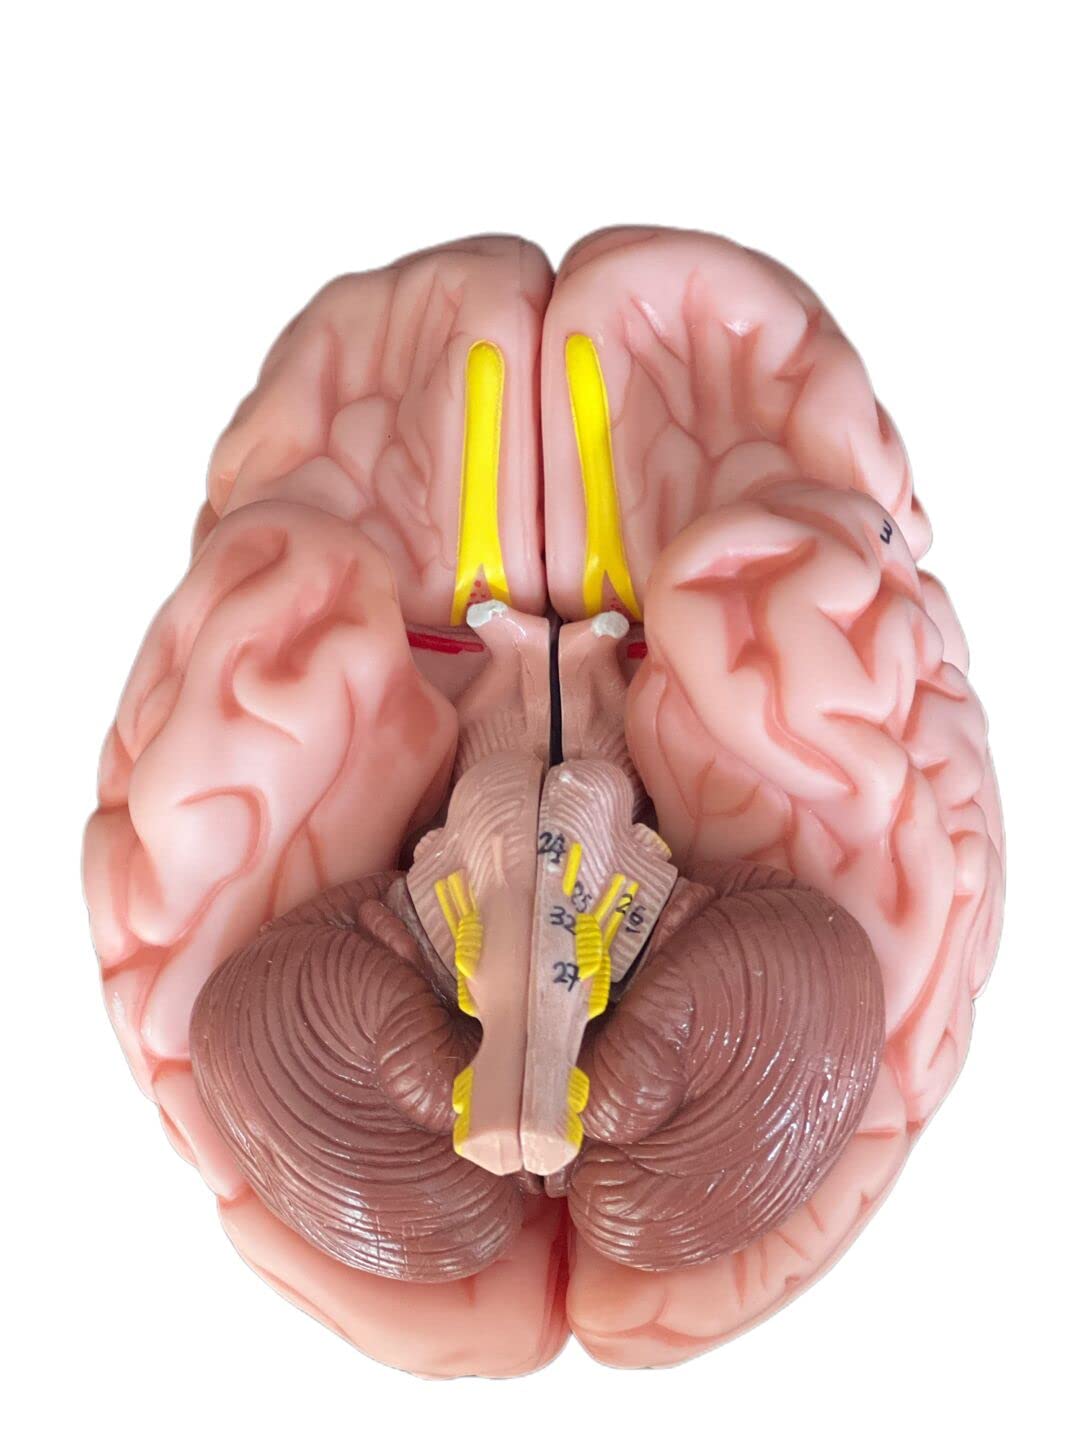

This model is cast from a high-quality original specimen. The classic skull is medically detailed in structure. It has highly accurate representation of the fissures, foramina, processes, sutures etc. Skull is 3-part: Skull Cap, Base of Skull and Mandible. The mandible is articulated on springs to demonstrate natural movements. Use this unique transparent replica of the human skull to study internal structures that otherwise are visible only through x-ray images. Brain separates into 8 parts: frontal and parietal lobes (2), temporal and occipital lobes (2), medulla (2), cerebellum (2). Structures are shown in great detail with about 30 features marked with numbers. Number key is provided. A great addition to any educational collection. Size: Life size Measurement: 22X13X17cm Weight: 2 kgs Material: high quality PVC

- The brain can be disassembled into 8 parts.